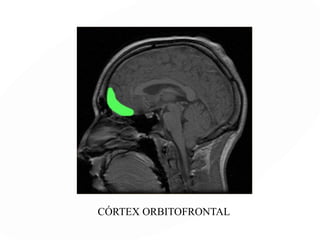

Lóbulos frontales

Orbitofrontal: zonas 10.11.12

Conductas delictivas, agresividad

CORTEZA FRONTAL DORSO-LATERAL

CÓRTEX ORBITOFRONTAL